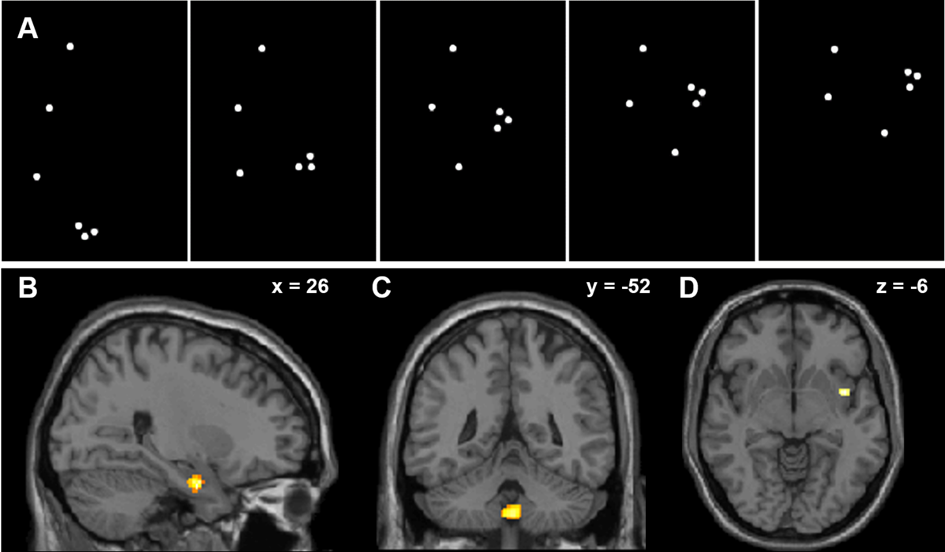

Neutrales und emotionales Punktlichtklopfen löst unterschiedliche Gehirnreaktionen aus. (A) Fünf Bilder veranschaulichen das Klopfen als eine Reihe von hellen Punkten auf einem dunklen Hintergrund. Die Punkte wurden auf dem Kopf, der rechten Schulter, dem Ellbogen, dem Handgelenk sowie dem ersten und vierten Mittelhandgelenk einer unsichtbaren, nach rechts gedrehten Person platziert. (B-D) Im Vergleich zu emotionalem Klopfen aktiviert neutrales Klopfen (B) die rechte Amygdala (x = 26; y = 4; z = -26, Koordinaten des Montreal Neurological Institute, MNI) und (C) die Mittellinie der Kleinhirn-Uvula (x = 0; y = -52; z = -46). (D) Die rechte Insula (x = 44; y = 4; z = -6) zeigt im Vergleich zu neutralen Klopfreizen eine höhere Aktivierung für emotionale Stimuli. Die Aktivierung wird auf die MNI T1-Vorlage überlagert. Die Schnittpositionen im MNI-Raum sind in der rechten oberen Ecke jedes Panels angegeben. Aus Sokolov et al. (2020). Proc Natl Acad Sci U S A. 117(34):20868-73.

Wie schließen wir auf das Fehlen von Emotionen in der Körpersprache? Im Gegensatz zur Erkennung emotionaler Signale ist die Frage, wie neutrale Körpersprache als solche erkannt wird, in den Neurowissenschaften noch kaum beantwortet. Allerdings ist sie von großer Relevanz für die Forschung im Bereich psychischer und neurologischer Erkrankungen, bei denen neutrale Signale als emotional fehlinterpretiert werden (wie etwa Autismus, Depression, Demenz oder Schizophrenie). Die funktionelle Kernspintomografie (fMRT) und das sog. Dynamische Kausale Modellieren (DCM) beleuchten den Zusammenhang neuronaler Kommunikation zwischen Amygdala und Insula mit unserer Fähigkeit, das Fehlen von Emotionen zu erkennen. Die Kommunikation zwischen der rechten Amygdala und der Inselregion kann nämlich vorhersagen, ob ein neutraler Ausdruck durch Körperbewegungen (hier Handklopfen) richtig erkannt wird. Bisher wurde angenommen, dass diese Bestandteile des limbischen Systems ausschließlich zur Wahrnehmung von Emotionen beitragen. Weiterführende Studien könnten neue Verfahren zur Diagnostik und Behandlung nach sich ziehen.